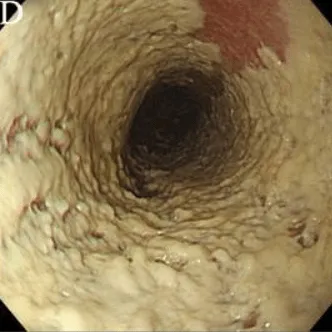

Степень II

Множественные приподнятые белесоватые бляшки размерами более чем 2 мм в диаметре с гиперемией вокруг, но без отека или язв